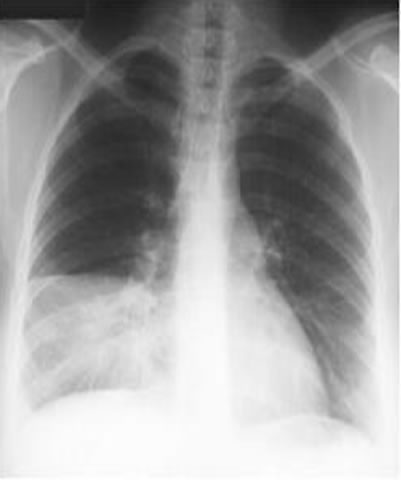

Pneumonie lobaire inférieure droite de face |

Pneumonie lobaire inférieure droite de profil |